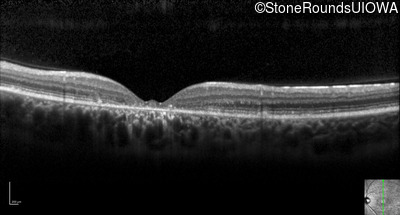

Optical Coherence Tomography - Right - 20/50 +2

Exemplar / OCT Stack